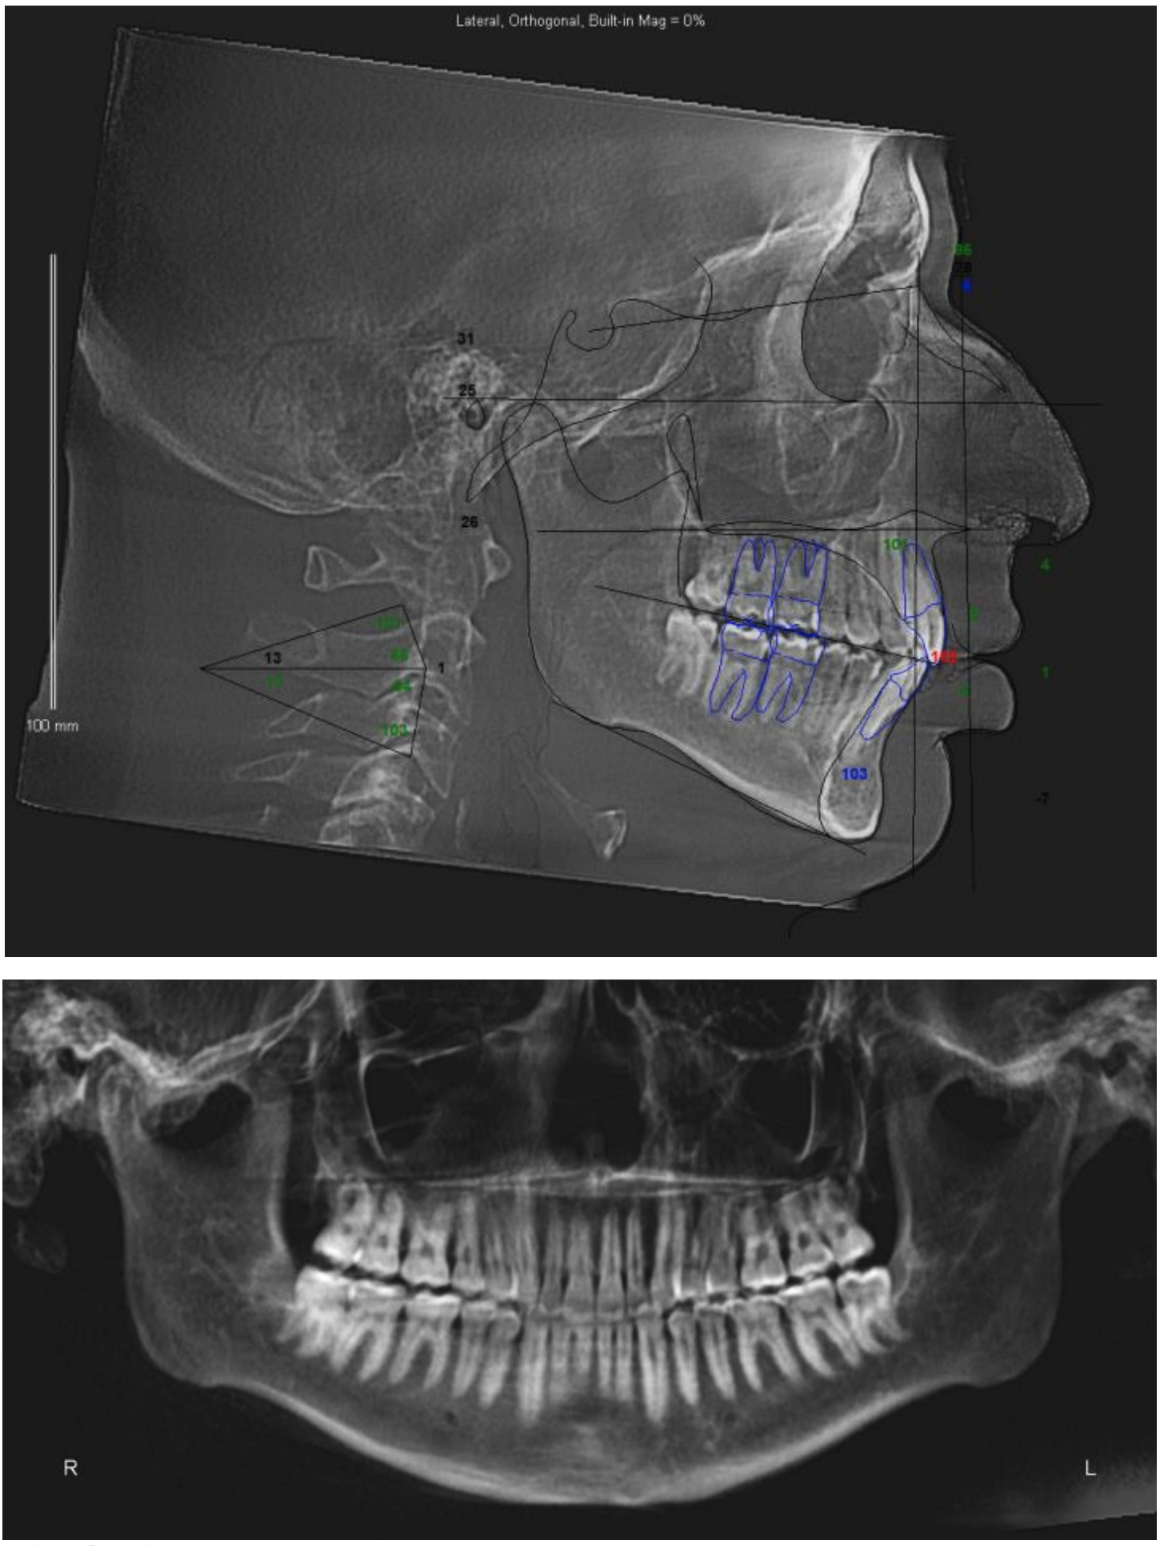

They are planning on doing a segmental 3-piece Lefort 1 which should give me about 5mm of expansion and 8mm of advancement, along with a CCW rotation of a few degrees (my dumbass forgot to ask how many) and a BSSO mandibular advancement of 12mm.

Feel free to ask any questions, also if any autists out there want to make comments about my scans, current appearance and my surgery plans then please do so.